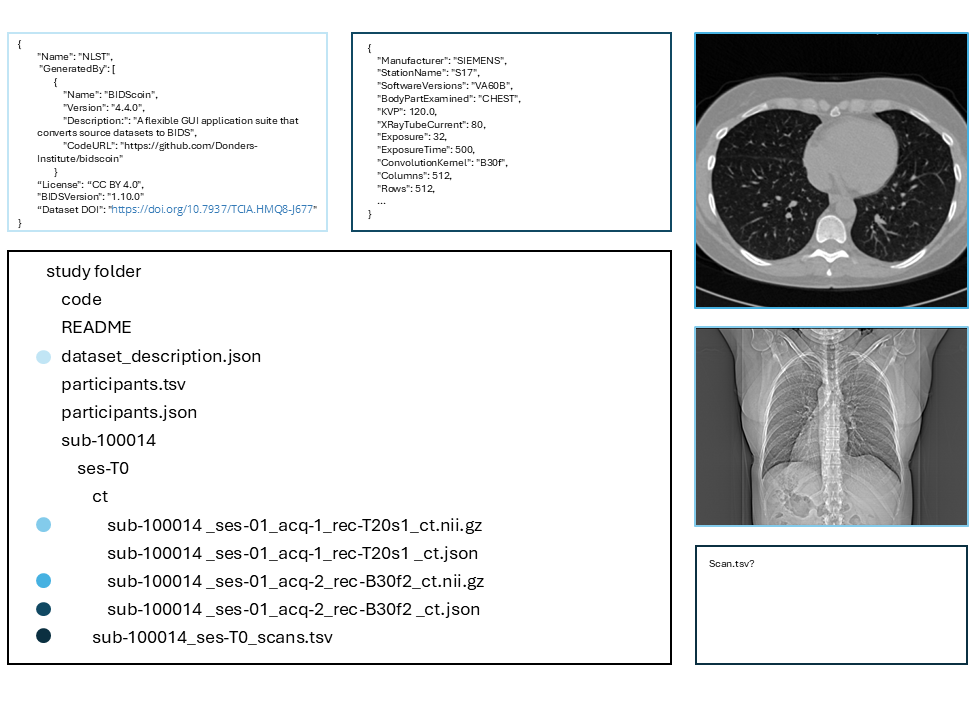

We present a proof-of-concept for the extension of the Brain Imaging Data Structure (BIDS) to accommodate Computed Tomography (CT) data. With the growing volume of CT imaging across various medical fields, including neuroradiology and thoracic imaging, the need for data standardization is increasingly critical, especially in the context of artificial intelligence (AI) tools for medicine. This study demonstrates the conversion of OASIS-3 and National Lung Screening Trial (NLST) datasets into BIDS format and the development of a BIDS App for lung cancer risk prediction using the Sybil AI tool. The resulting framework promotes interoperable, accessible, and reusable data, fostering Open Science and enabling independent validation of AI models across diverse systems and datasets, ultimately addressing challenges like bias and overfitting in clinical settings.Clinical relevanceThis study enables the sharing and reuse of CT data within the research community, enhancing knowledge extraction and accelerating the development and validation of AI tools that can improve diagnostic accuracy and clinical decision-making across various medical fields.